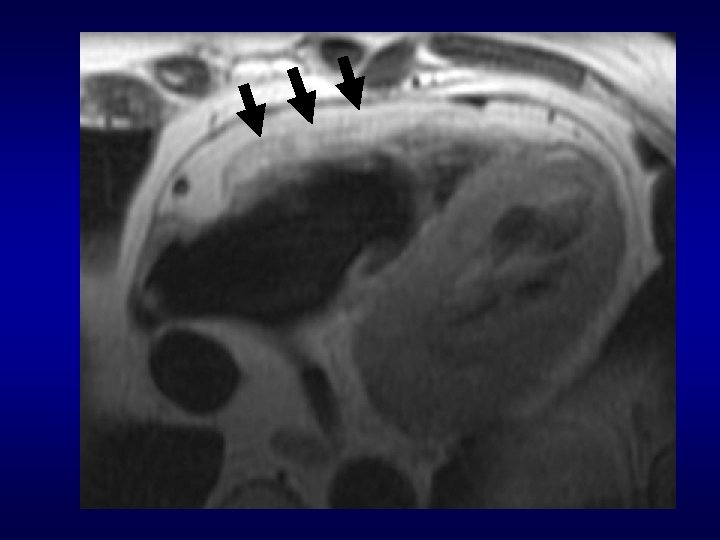

ARVD: findings on axial images Aortic valve level Mid ventricular level 38 yo F, athlete with ventricular tachycardia

RV enlargement: differential diagnosis in the setting of suspected ARVD 1. Normal variant (young age) 2. Pulmonary Hypertension 3. PAPVR 4. Intracardiac shunt or valve dysfunction

RV and Pulmonary outflow tract enlarged, poor function

Right ventricular aneurysm Typical ARVD